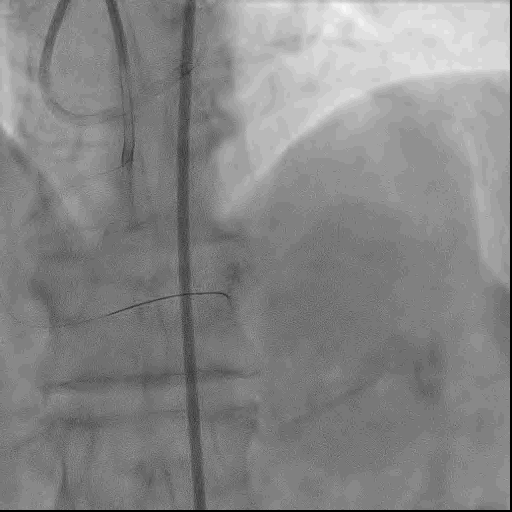

故采用DK-CRUSH策略于LAD和LCX分别植入支架,术后复查冠脉造影可见LAD及LCX开口无残余狭窄,血流良好。

● LAD-CTO病变开通后LAD开口残余狭窄80%,同时LCX开口狭窄程度也较重,约70-80%,为真性左主干分叉病变。对于这种类型的分叉病变,首选双支架策略。术者选择了DK-CRUSH策略,于LAD和LCX分别置入支架,术后复查造影LAD和LCX也确实得到了明显的改善。